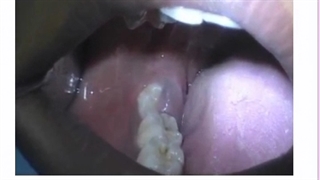

جراحی دندان عقل (بخش اول)